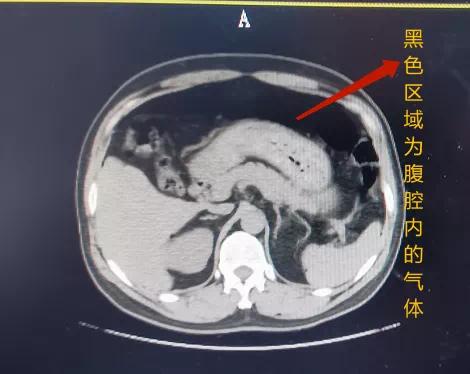

高压气体一旦进入人体

首先遭殃的就是 直肠、结肠、盲肠

别看它们加起来的长度

可 正常厚度也只有 1-4mm